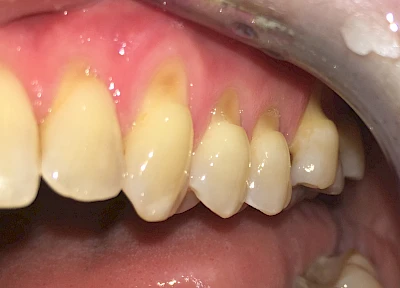

Eine Sonderform sind sogenannte keilförmige Defekte im Bereich der Zahnhälse. Hier geht man davon aus, dass Knirschen und Pressen in Kombination mit falschen Putzgewohnheiten (zu hoher Putzdruck, Verwendung von Zahnpasta mit hohen Abrasionswerten) eine Rolle spielen.